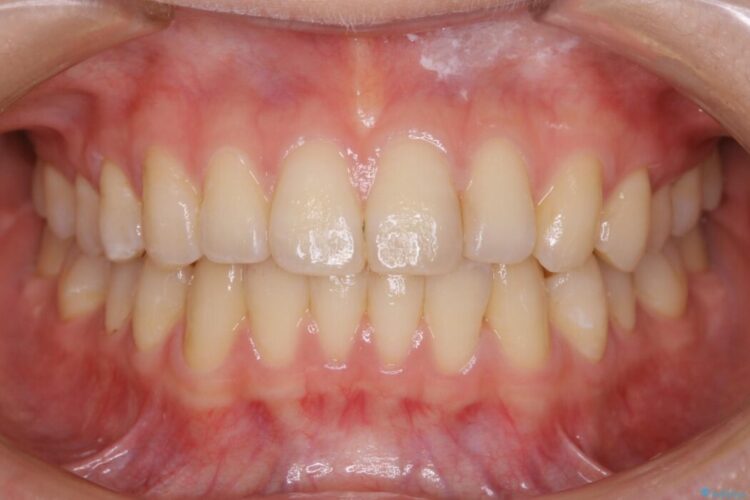

下額前歯が少しガタついていることを気にされて来院されました。

検査をしたところ奥歯の噛み合わせなどに問題が見られなかったため、軽度のねじれがある下顎前歯に焦点を当てた部分矯正の適応が可能と判断し、インビザラインのライトパッケージをご提案しました。

本症例では奥歯に関して問題がほぼ見られなかったため、部分矯正を行うことが可能と判断しました。